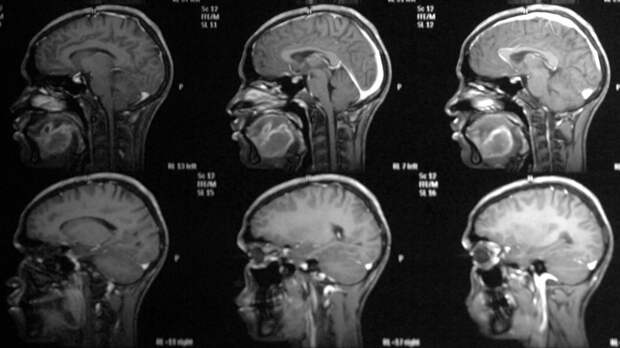

Онколог-хирург, кандидат медицинских наук Михаил Мяснянкин в интервью «Пятому каналу» перечислил наиболее распространённые симптомы рака головного мозга.

Он отметил, что болезнь непросто определить на ранних стадиях из-за бессимптомного течения.

Среди признаков, которые появляются позже, онколог назвал быструю утомляемость, головокружения, тошноту, потерю сознания, судороги, а также ухудшение зрения и слуха.

«Самым распространённым симптомом опухоли головного мозга является головная боль. При поражении органов, отвечающих за вестибулярную функцию, начинают проявляться нарушения письменной речи, звукопроизношения, при речи могут выпадать словосочетания, буквы», — рассказал врач.